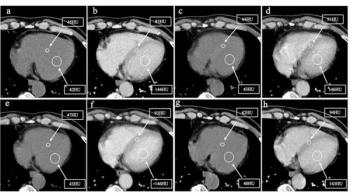

Nine months after initiation of androgen deprivation therapy (ADT), prostate cancer patients with higher myocardial extracellular volume (ECV) — derived from chest contrast-enhanced CT — had over a fourfold higher risk for major adverse cardiovascular events (MACEs), according to new research.